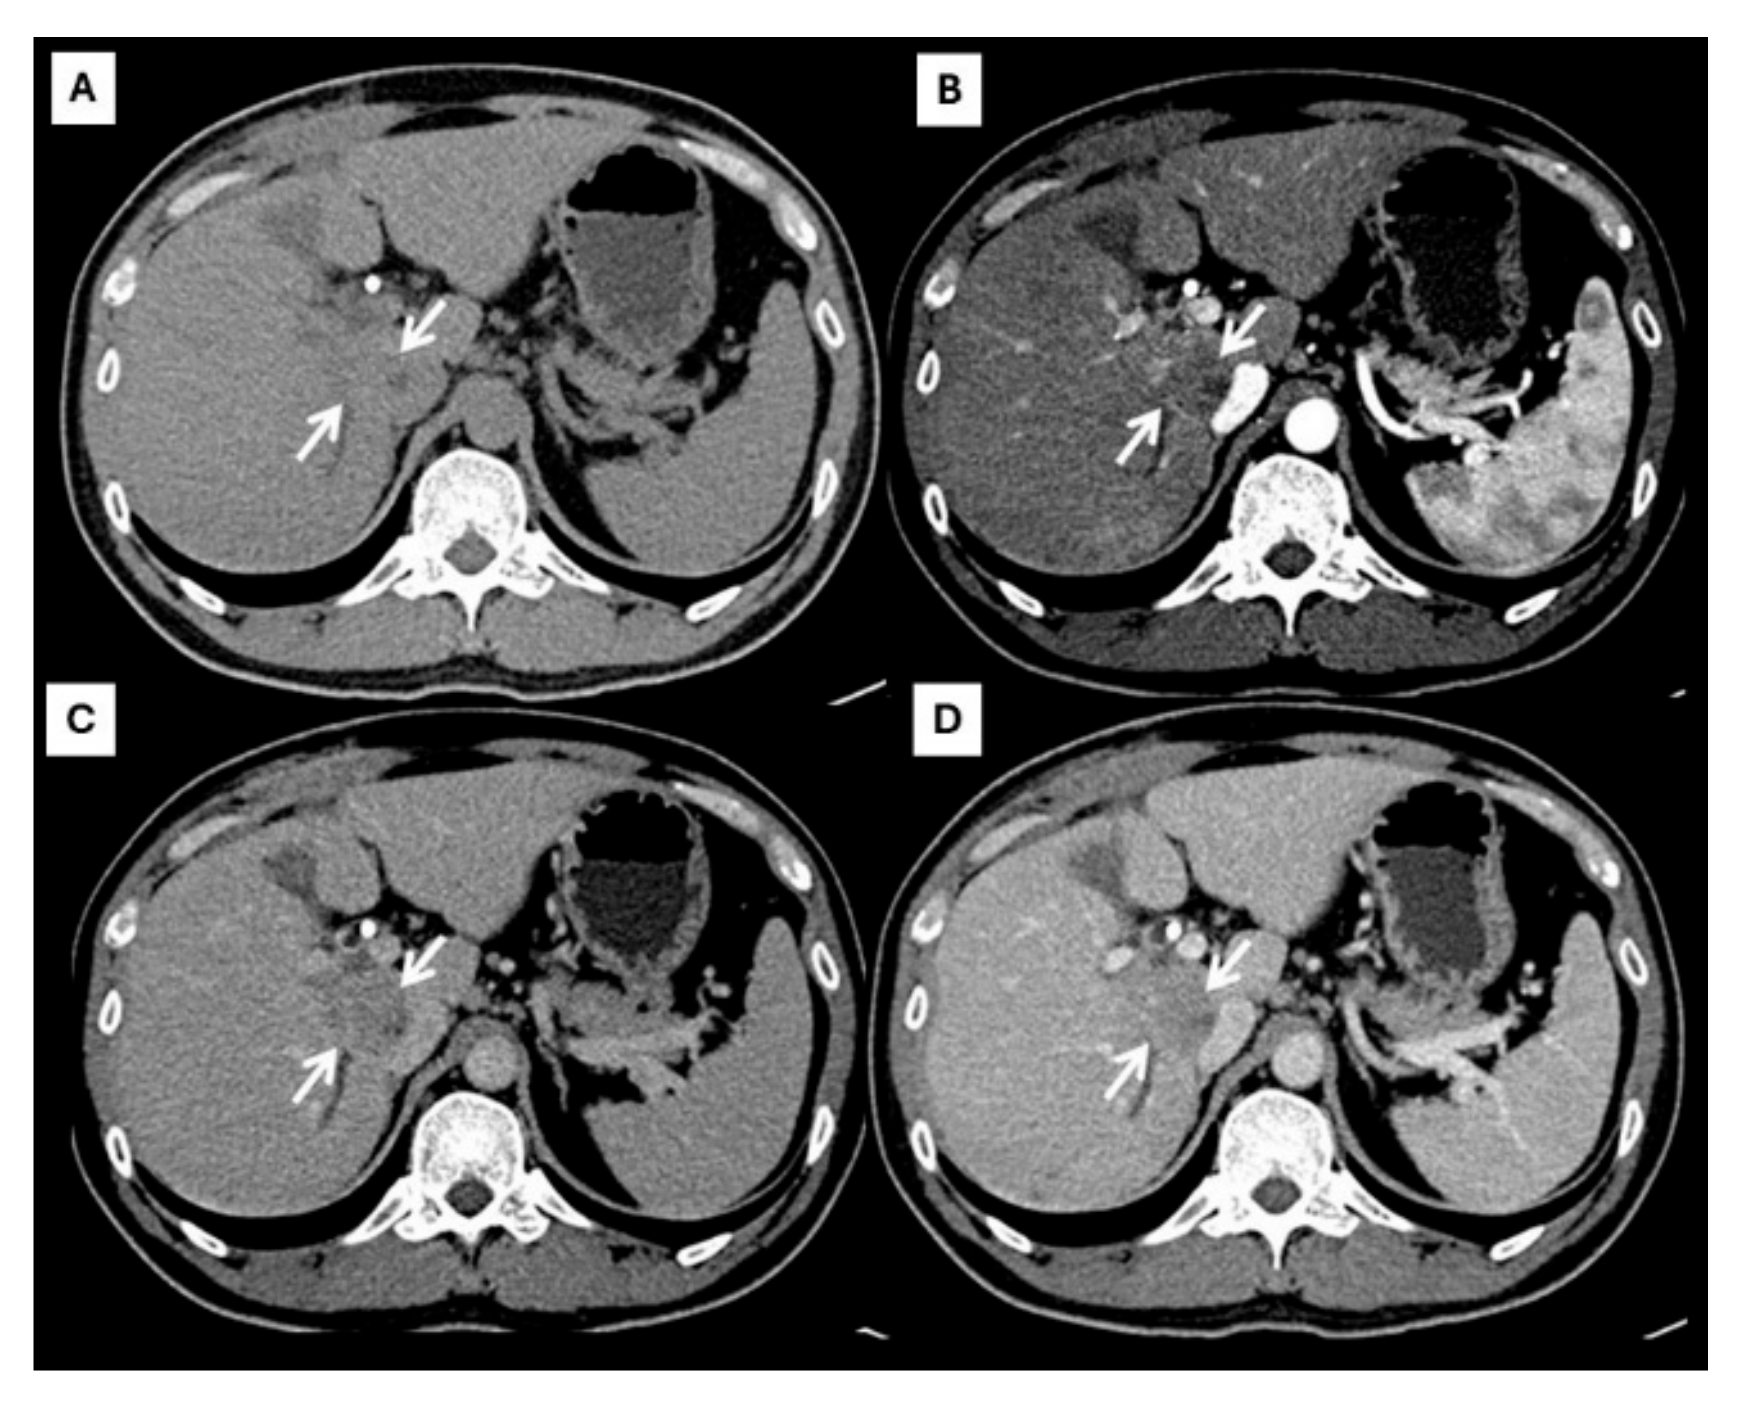

| Later arterial phase | Arterial phase hyperenhancement | Rim-like enhancement |

| Portavenous phase | Non-peripheral washout | Progressive peripheral enhancement |

| Delayed phase | Capsule enhancement | Progressive peripheral enhancement |